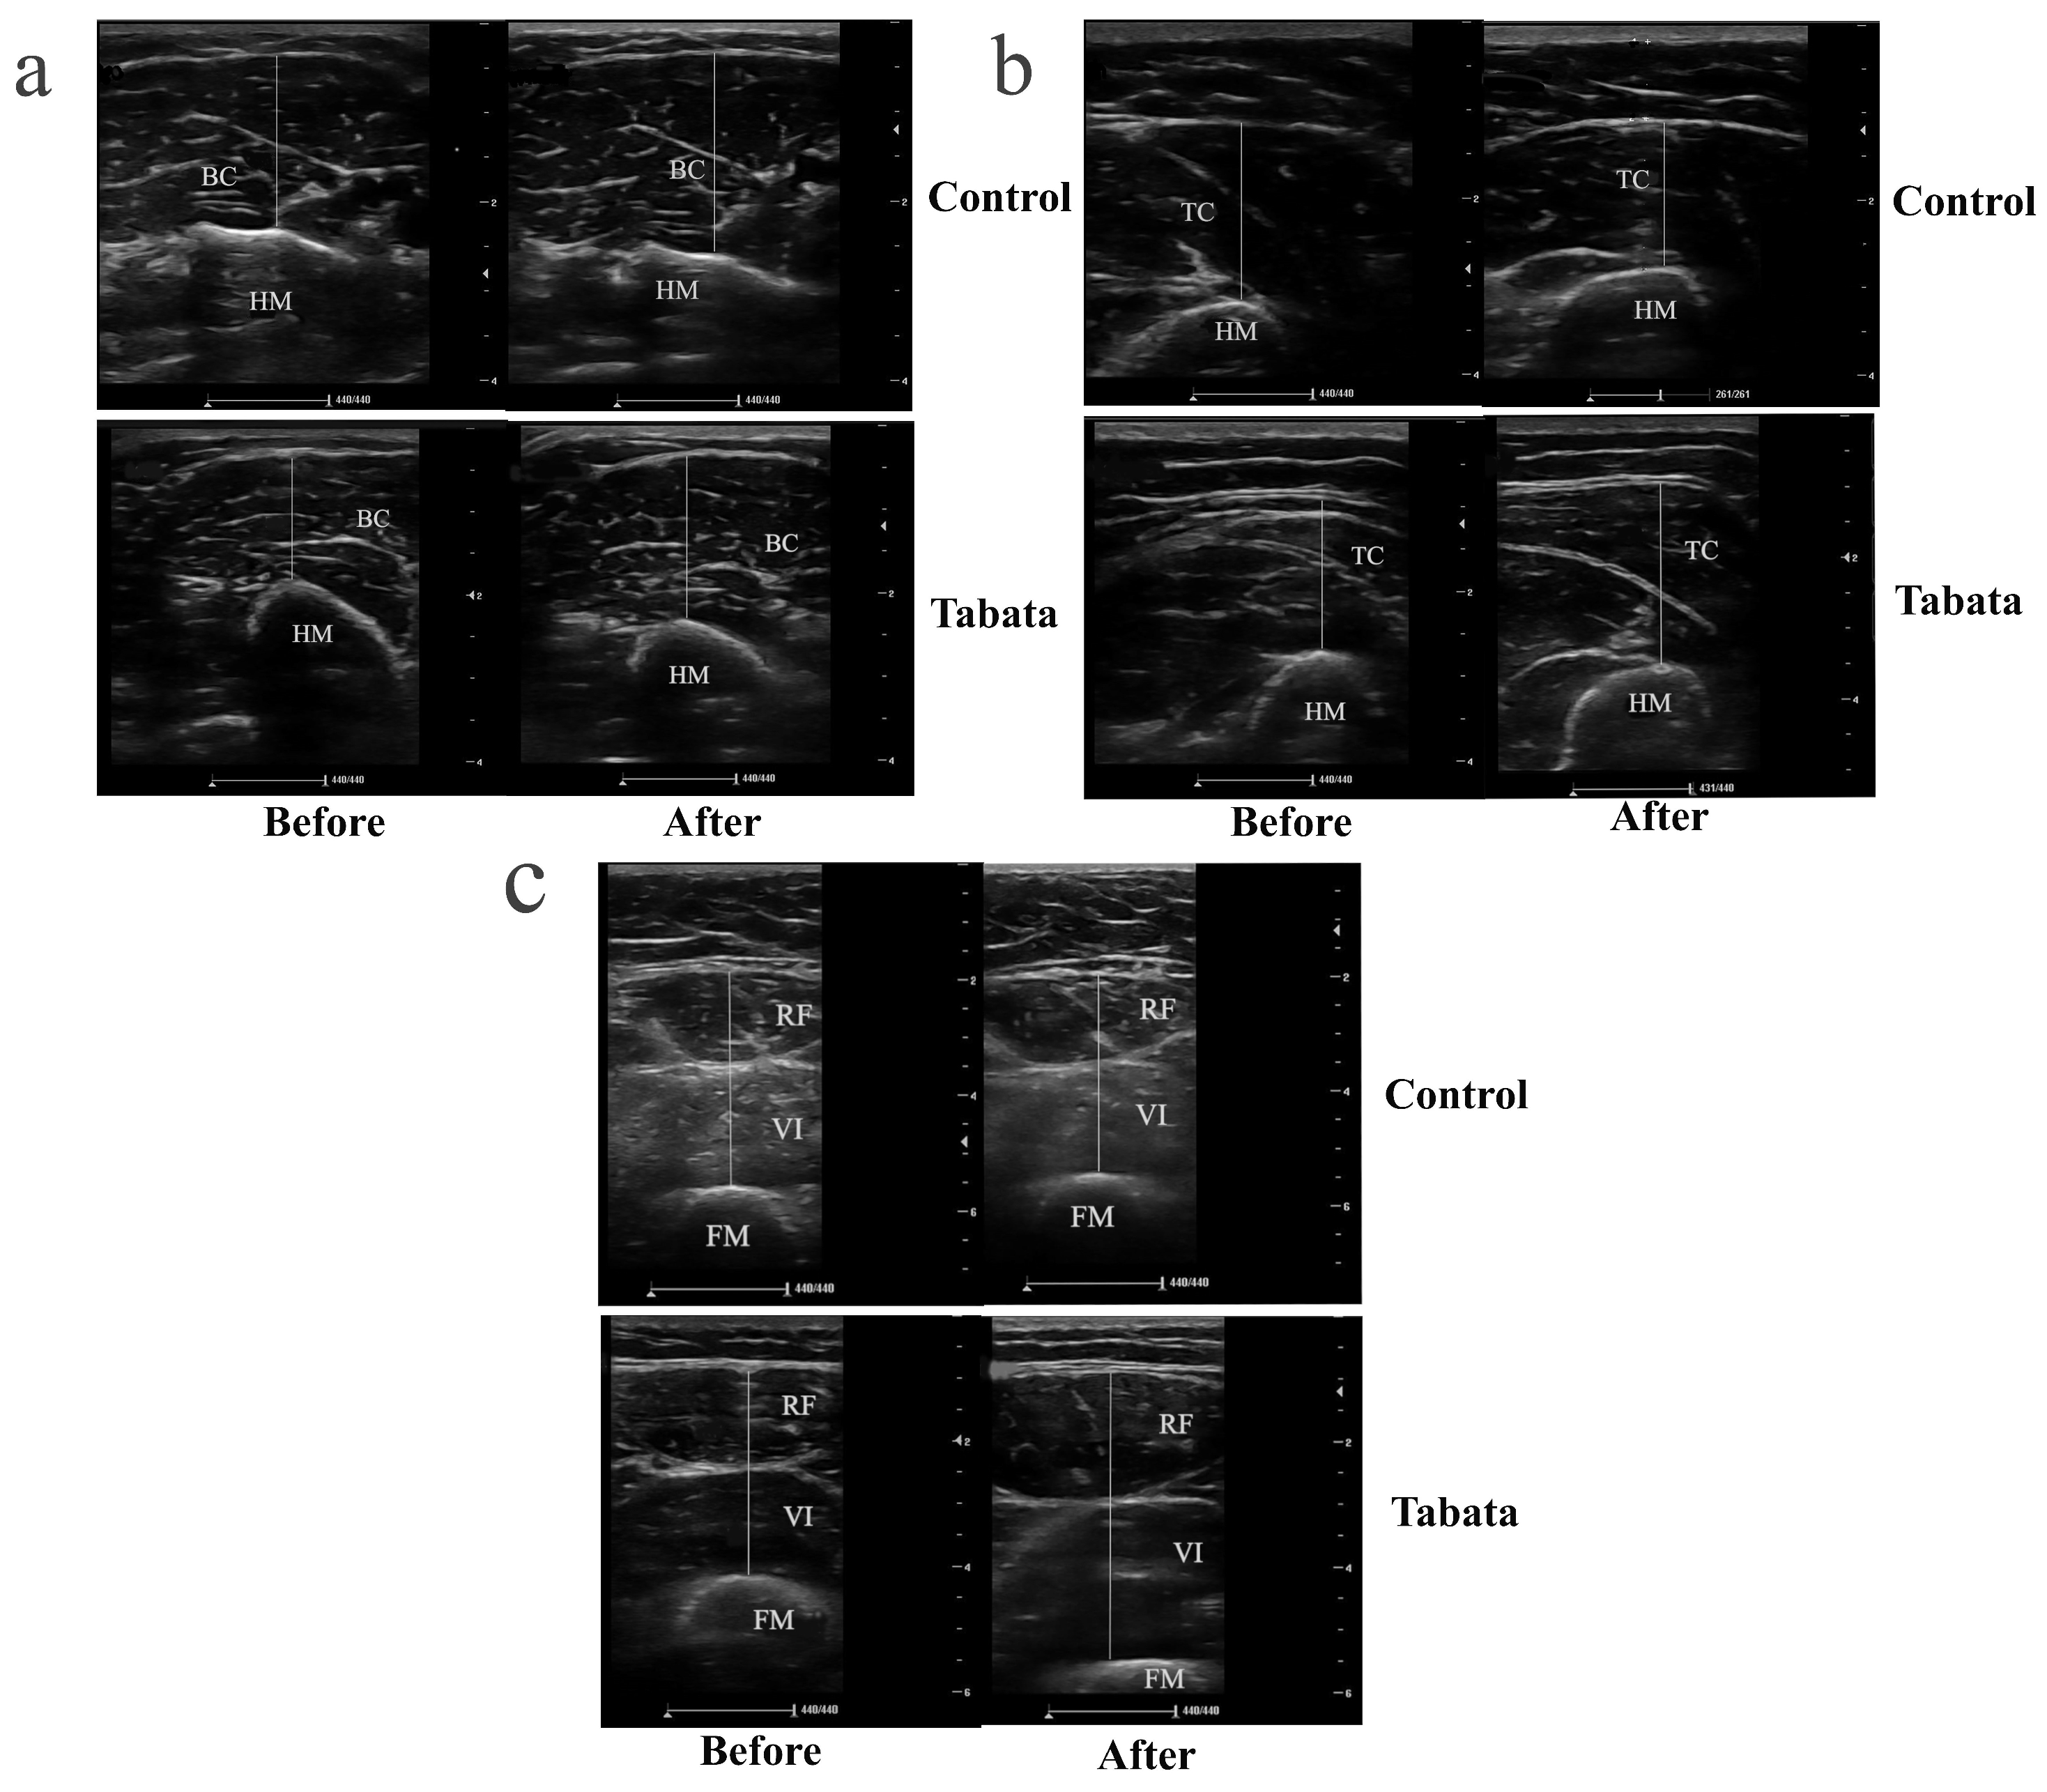

2.5.2. Muscle Thickness

3.3. Impact on Muscle Thickness

4.2. Modified Tabata Training Improves Muscle Thickness